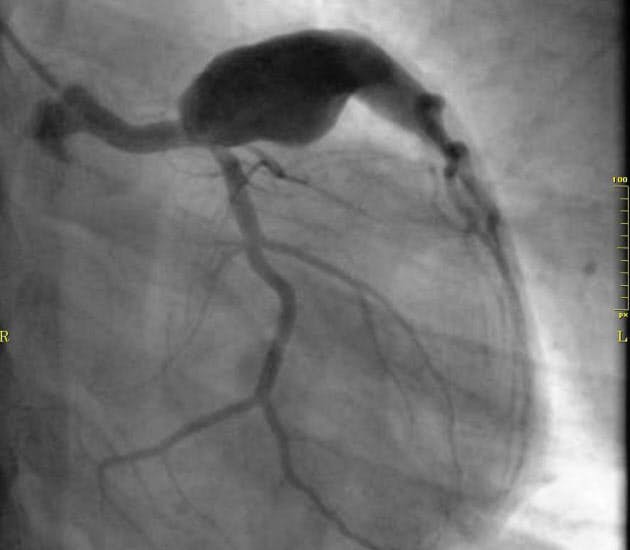

川崎病 冠動脈病変 電子コンテンツ 日本医事新報社

川崎病急性期診療における小児冠動脈内径zスコアの活用法について Jbスクエア 日本血液製剤機構 医療関係者向け情報

川崎病の合併症とは 大きな冠動脈瘤が生じる危険 メディカルノート

川崎病の合併症に関する最新研究 後遺症ゼロを目指して メディカルノート